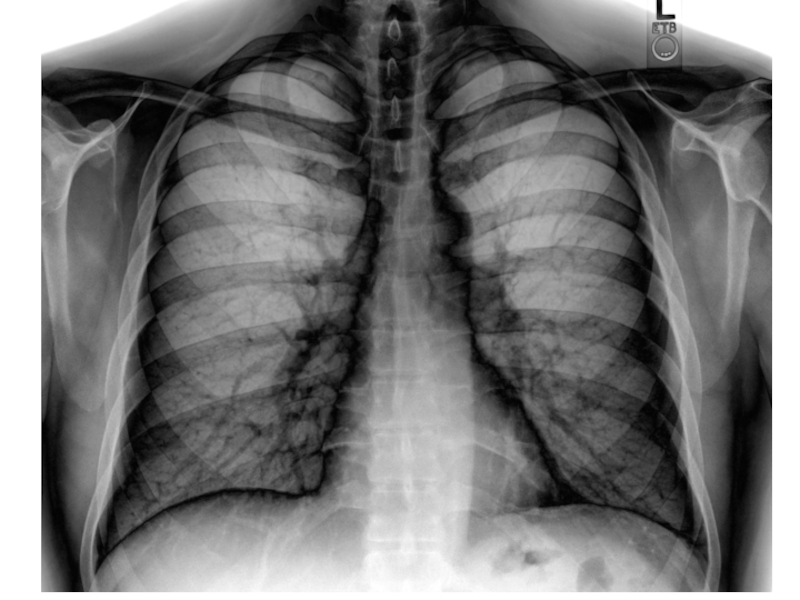

Слайд 38Структуры, различимые на рентгенограмме легких

Легочные поля

Тень средостения

Костные концы ребер

Межреберные промежутки

Ключицы

Корни

легких

Синусы плевры

Структуры, различимые на рентгенограмме легкихЛегочные поляТень средостенияКостные концы реберМежреберные промежуткиКлючицыКорни легкихСинусы плевры

Слайд 39Рентгенограмма легких

Рентгенограмма легких